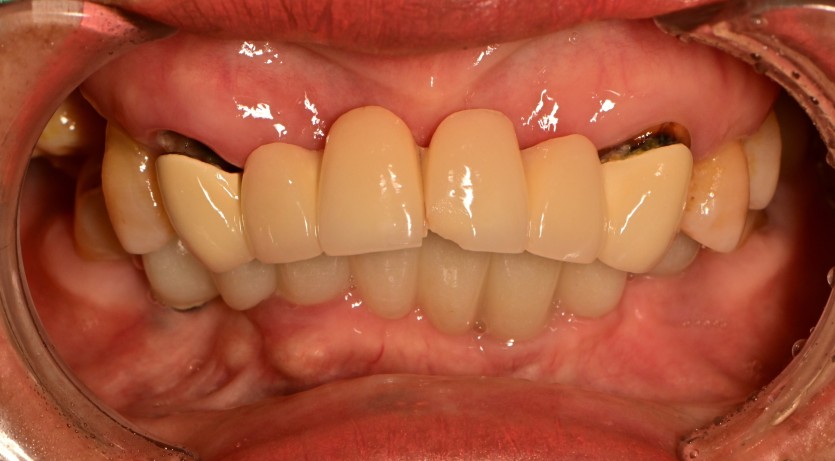

상악 전체 임플란트 증례입니다.(하악 일부)

11개의 임플란트로 완성하였습니다.